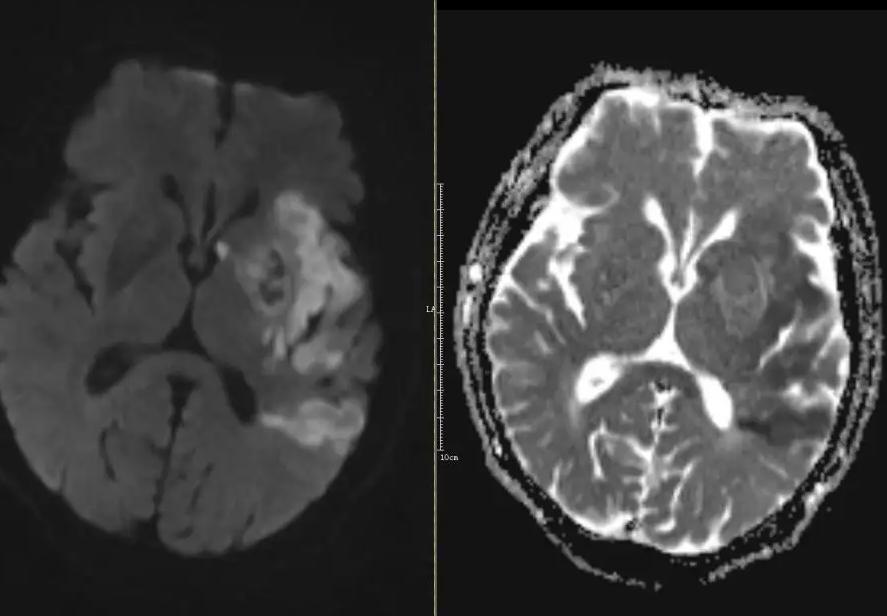

话说有这样一位患者郭先生,55岁,来看诊的3天前夜间卧床休息时,突感言语不清,发音费力,右侧上、下肢体难以活动,乏力明显。家属及时发现送至当地三甲医院,急做头颅CT检查后诊断“急性脑梗死”,给予溶栓治疗。病程中,郭先生意识清晰,无其他明显不适,但言语不清未见改善,右侧肢体仍无力,甚至有加重趋势。主诉:言语不清伴右侧肢体无力3天。